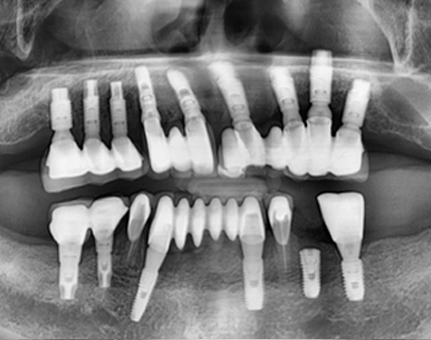

문치과 임플란트 사례

모든 전후 사진은 단순한 비교가 아닌,

환자분의 고민과 변화의 기록입니다.

문치과는 각자의 사연에 맞는 해답을 찾습니다.